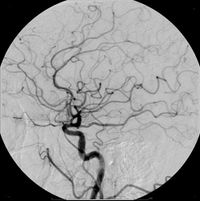

مثالٌ آخر على المادة المظللة، هنا حُقنت المادة المظللة في الأوعية الدموية الدماغية، وظهرت بشكل واضح، شاهد أيضاً القسطرة الشريانية